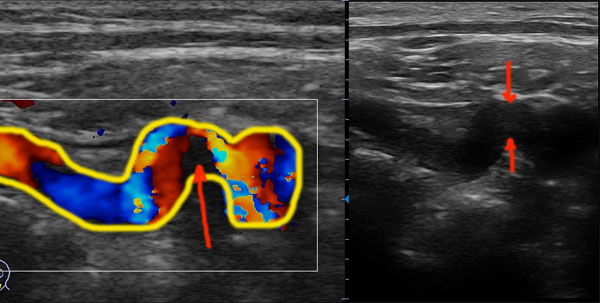

Женщина 62 лет, жалобы на головные боли.

Какое, на ваше мнение, можно выставить УЗ-заключение?!

Стенозирующий атеросклероз ПА, гемодинамически значимый.

Дугообразная извитость ПА в V1.

В описании указал АСБ в устье ПА со стенозом до 70%

Угол подъемы на извитости Па острый и угол пришлось выставлять такой же острый.

В третьем сегменте ЛСК - 30 см/сек.

В АСБ не верю. И это не S образная извитость - а кинкинг. А АСБ V0 надо доказывать... А скорости и в ПА ого какие бывают...Вот...